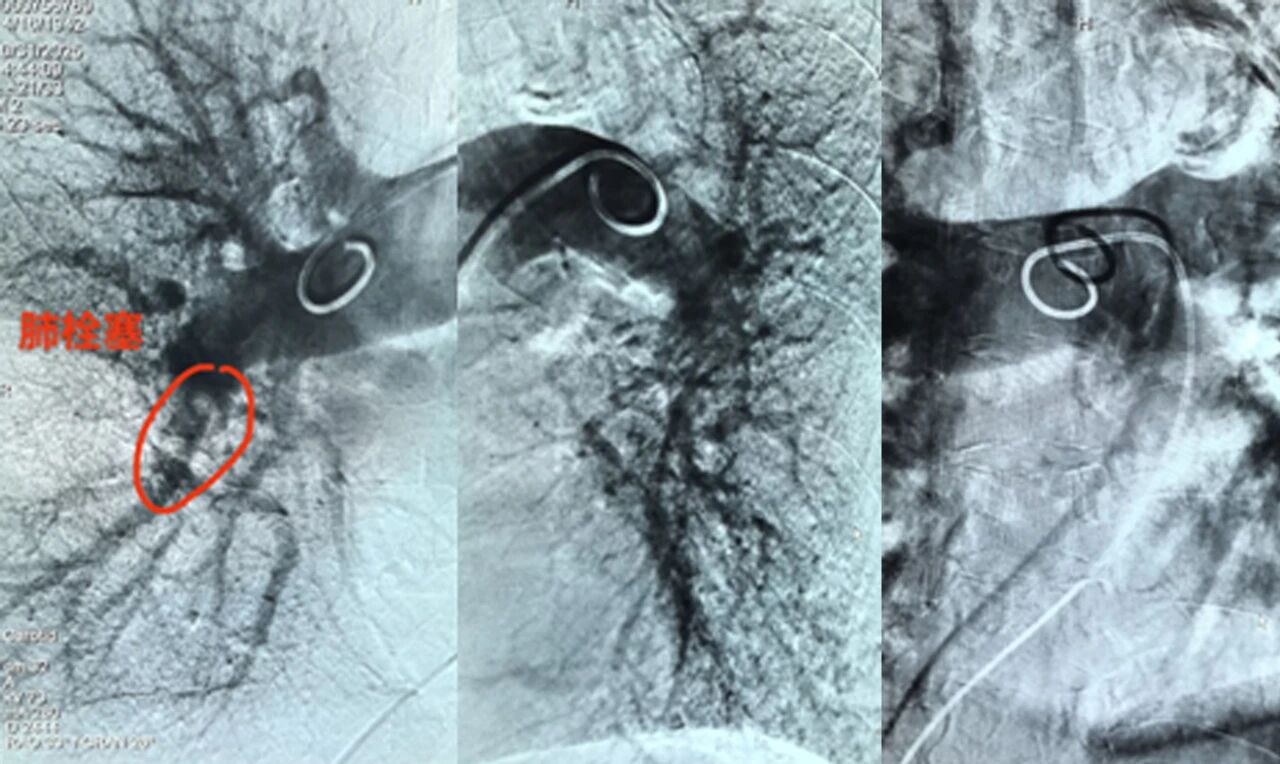

近日,沧州市第四医院(南皮县人民医院)成功开展首例肺动脉造影+溶栓术,此项技术填补了医院肺血管介入领域的空白,标志着我院急性肺栓塞救治水平达到全省同级医院先进行列,为高危肺栓塞、慢性血栓栓塞性肺动脉高压患者提供了精准治疗新选择,进一步提升区域内急危重症救治效率。

患者为一83岁女性,因肢体活动后出现呼吸困难,症状一直持续3天,后入院经CT肺动脉成像检查确诊为“急性肺栓塞”,病情危急,随时面临呼吸循环衰竭的生命危险。

面对这一紧急情况,心血管内二科邢文华主任带领介入团队密切协作,迅速制定个性化手术方案,术中精准操作导管,在30分钟内完成血栓定位与溶栓药物输注。术后密切监测患者生命体征,提供24小时精细化护理,确保患者平稳恢复。

肺动脉造影术作为一种精准、微创的检查手段,能够清晰显示肺动脉的形态、结构以及血流状况,为医生准确诊断肺部疾病提供了关键线索。无论是复杂的肺动脉栓塞,还是难以察觉的肺动脉狭窄、肺血管畸形等疾病,肺动脉造影术都是其诊断的金标准。

此次肺动脉造影+溶栓术,通过微创介入技术,实现“精准诊断+靶向治疗”的一体化,突出表现以下三方面。

一是精准定位:在数字减影血管造影(DSA)引导下,医生将导管直达肺动脉栓塞部位,清晰显示血栓位置、大小及阻塞程度,避免了传统检查的盲区。

二是靶向溶栓:通过导管直接向血栓内注入溶栓药物,药物浓度高、作用直接,可快速溶解血栓,恢复肺血流,同时显著降低全身出血风险。